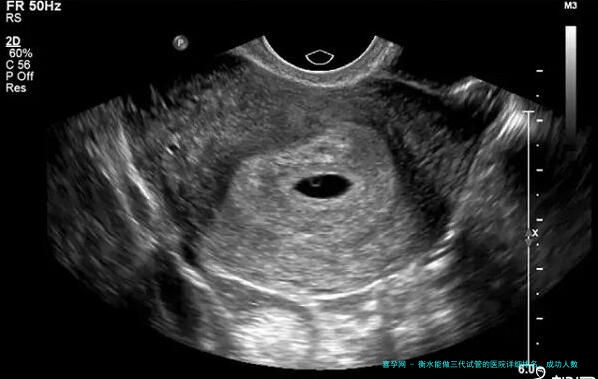

衡水市一级医院、衡水市重点医院和衡水市生育保健院均配配置有先进的医疗设备和装置,在进行三代试管手术时可以提供全面性、高素质的服务。在检查诊断环节这些医院具有各类先进设备如超声仪、内镜等,可以全方位了解患者身体情况。